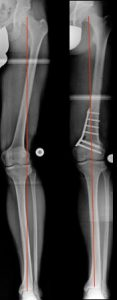

Aufklappende Korrekturosteotomie, kniegelenksnah am Schienbein, bei O-Bein und innenseitige Arthrose. Der „offene“ keil füllt sich im Rahmen der Callusbildung mit körpereigenen Knochen auf (Bild 8).

Beidseitige, zuklappende Korrekturosteotomie, kniegelenksnah am Oberschenkel bei X-Bein und fortgeschrittener Arthrose (Bild 9).

Bemerkenswert ist die „Öffnung“ des äußeren Gelenkspaltes, am rechten Bein, durch die Lastumverteilungsmaßnahme. Korrekturen wie diese adressieren nicht nur Knie- sondern auch Beinschmerz.

Sie dienen gleichzeitig der Vereinfachung einer später eventuell notwendigen Versorgung mit einer Gelenkprothese.